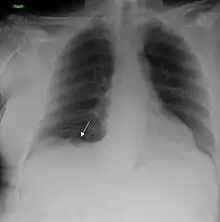

Performing a chest radiograph is one of the first investigative steps if a person reports symptoms that may be suggestive of lung cancer. This may reveal an obvious mass, the widening of the mediastinum (suggestive of spread to lymph nodes there), atelectasis (lung collapse), consolidation (pneumonia), or pleural effusion.[15] CT imaging of the chest may reveal a spiculated mass which is highly suggestive of lung cancer, and is also used to provide more information about the type and extent of disease. Bronchoscopic or CT-guided biopsy is often used to sample the tumor for histopathology.[13]

Lung cancer often appears as a solitary pulmonary nodule on a chest radiograph. However, the differential diagnosis is wide. Many other diseases can also give this appearance, including metastatic cancer, hamartomas, and infectious granulomas caused by tuberculosis, histoplasmosis or coccidioidomycosis.[65] Lung cancer can also be an incidental finding, as a solitary pulmonary nodule on a chest radiograph or CT scan done for an unrelated reason.[66] The definitive diagnosis of lung cancer is based on the histological examination of the suspicious tissue[2] in the context of the clinical and radiological features.[12]